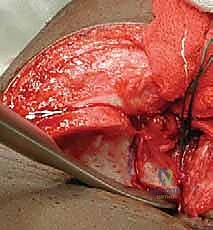

يقوم الجراح بإجراء قطع غير كامل في عظم الحوض (عظم الحرقفة) يمتد وصولاً إلى الغضروف ثلاثي الشعب (Triradiate Cartilage) الذي يكون مرناً لدى الأطفال. هذا الغضروف يعمل كـ "مفصلة" (Hinge). يتم بعد ذلك ثني سقف التجويف الحقي إلى الأسفل والخارج لتغطية رأس الفخذ من الجهة الأمامية الجانبية (Anterolateral).

تُعد هذه التقنية ممتازة للأطفال الذين يعانون من نقص شديد في التغطية الأمامية لرأس الفخذ، وعادة ما تُجرى للأطفال بين عمر سنة ونصف إلى 6 سنوات، قبل أن يتعظم الغضروف ثلاثي الشعب. للحفاظ على الوضعية الجديدة للسقف، يتم أخذ قطعة عظمية صغيرة (طعم عظمي - Bone Graft) من حوض الطفل نفسه ووضعها في مكان القطع كإسفين داعم.

في عملية ديجا، يتم قطع القشرة الخارجية لعظم الحرقفة مع ترك القشرة الداخلية سليمة لتعمل كمفصلة (Hinge). هذا يسمح للجراح بثني سقف الحُق إلى الأسفل بمرونة عالية، مما يوفر تغطية ممتازة لرأس الفخذ، خاصة من الجهة الخلفية الجانبية (Posterolateral).

4. الرد المفتوح (إن لزم الأمر):

إذا كان الورك مخلوعاً، يتم تنظيف التجويف الحقي من أي أنسجة ليفية أو دهنية تعيق دخول رأس الفخذ. ثم يتم إرجاع رأس الفخذ إلى مكانه الطبيعي برفق.

5. إجراء القطع العظمي (بيمبرتون أو ديجا):

باستخدام أدوات جراحية دقيقة جداً، يتم إجراء القطع العظمي في الحوض وثني سقف الحُق لتغطية رأس الفخذ بالزاوية المثالية التي تم التخطيط لها.

6. تثبيت المفصل وإغلاق الجرح:

يتم أخذ طعم عظمي من حوض المريض ووضعه في شق القطع العظمي لتثبيت السقف في وضعه الجديد. في بعض الحالات، قد تُستخدم دبابيس معدنية (K-wires) لتثبيت إضافي مؤقت. يتم إغلاق الجرح بخيوط تجميلية تذوب تلقائياً.